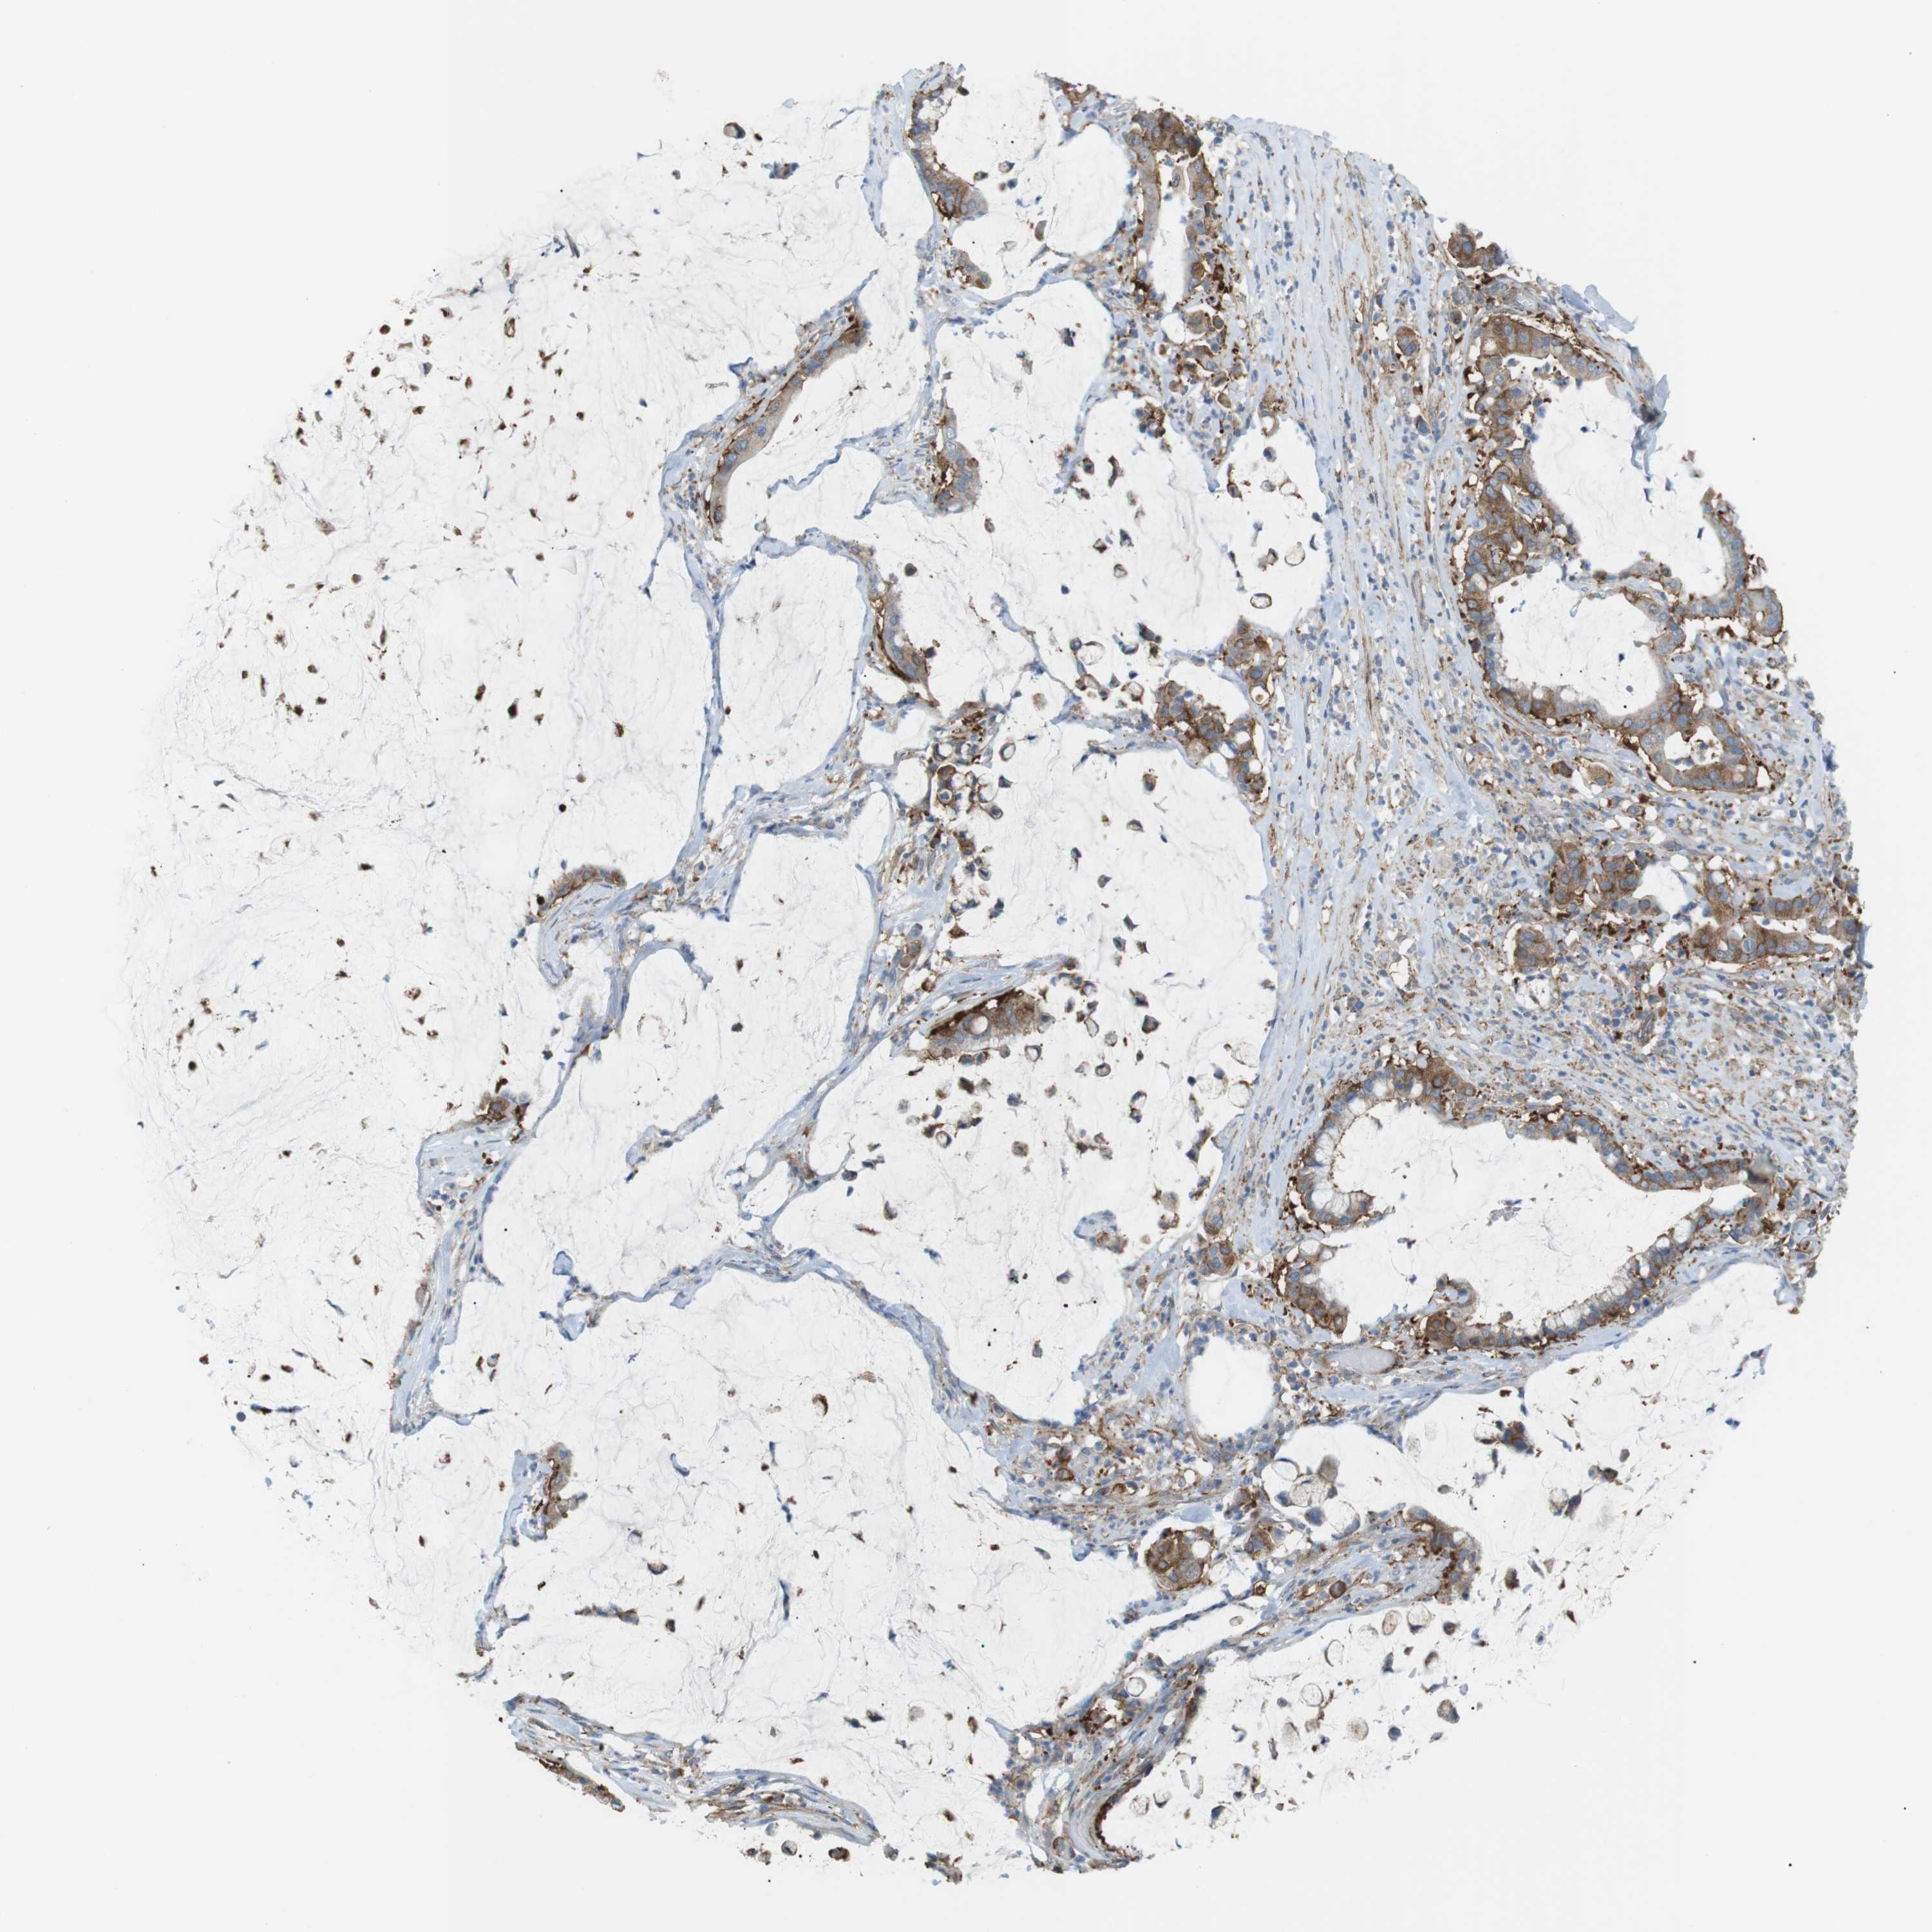

PANCREATIC CANCER - Protein expressioni

A mouse-over function shows sample information and annotation data. Click on an image to view it in a full screen mode. Samples can be filtered based on level of antibody staining by selecting one or several of the following categories: high, medium, low and not detected. The assay and annotation is described here.

Note that samples used for immunohistochemistry by the Human Protein Atlas do not correspond to samples in the TCGA dataset.

Antibody stainingi

Antibody staining in the annotated cell types in the current human tissue is reported as not detected, low, medium, or high, based on conventional immunohistochemistry profiling in selected tissues. This score is based on the combination of the staining intensity and fraction of stained cells.

Each image is clickable and will lead to virtual microscopy that enables deeper exploration of all samples and also displays staining intensity scores, fraction scores and subcellular localization as well as patient and tissue information for each sample.

Antibody HPA015599

Staining

High

Medium

Low

Not detected

Intensity

Strong

Moderate

Weak

Negative

Quantity

>75%

75%-25%

<25%

None

Location

Nuclear

Cytoplasmic/membranous

Cytoplasmic/membranous,nuclear

Adenocarcinoma, NOS